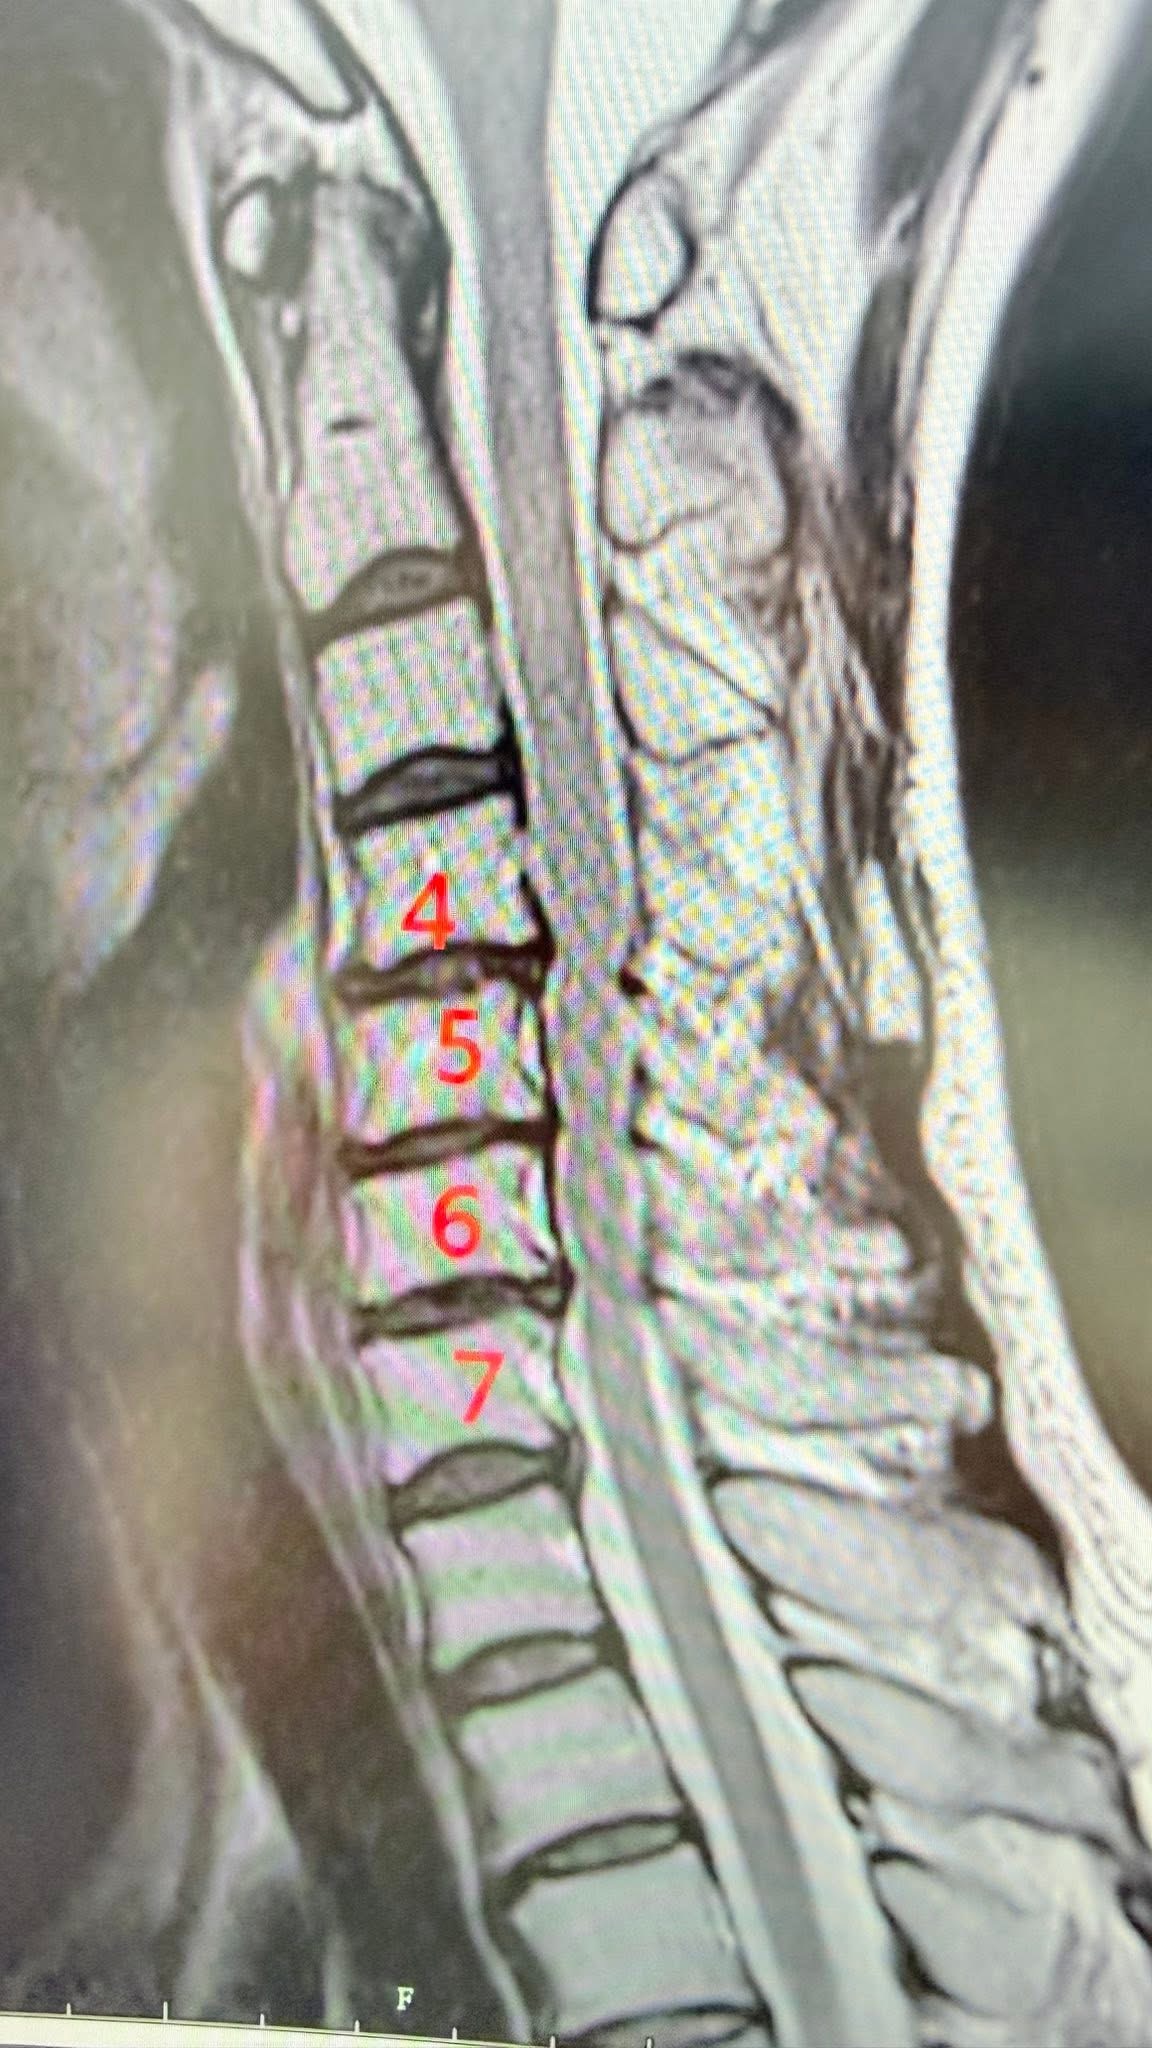

Cervical Spine Treatment Cases 頸椎治療案例 標題:當香港跟倫敦所有名醫都說頸椎必須開大刀:一位香港母親,如何在台北三週內逆轉... 2026.03.18 「徐國峰醫師的診間針刀筆記」 影像上的「死刑」,針尖下的「新生」:一個跨越 2500 ... 2026.03.03 飛鷹歸來:解開 9G 鎖喉的「脊椎減壓」奇蹟 —— F-16 飛官龔先生頸椎減壓針刀復原長... 2026.01.15 醫案深探:當頸椎失去靈魂的曲線,神經根在狹縫中求生。 深夜的痛覺,為什麼你的頸椎... 2026.01.11 「不是花粉!不是塵蟎!長年過敏性鼻炎的真正原因,可能藏在你的頸椎深層筋膜裡」 文... 2025.12.08 🌟新竹范小姐的頸椎奇蹟醫案分享 ——手術與非手術之間,她找到屬於自己的第三條路 ✅... 2025.12.03 脊椎噩夢兩年三開!花費新台幣三百萬元 頸椎手術黑洞蒸發公務員積蓄:300萬,換不回... 2025.11.21 ⭕️低頭的代價:智慧手機正在悄悄「鎖死」台灣八百萬長輩們的殘破頸椎 🛑頸椎人工椎間... 2025.11.06 跨越半個地球的希望:華僑黃阿姨的頸椎奇蹟。 美國頸椎手術ACDF要價台幣150-250萬。 ... 2025.10.03 【200公斤水泥的血淚啟示:揭開你頸椎上「慢性重量」的驚人真相與致命代價! 【⚠️ 醫... 2025.09.29 ❇️頸椎推拿的風險警鐘:從一個真實案例談起 ‼️電流竄過手臂的那一瞬間,他的人生被改... 【醫療案例探討真相|PRP打進頸椎椎間盤?一名患者一年的手腳無力,背後的風險不可不... 2025.08.16 🚨 MRI 一張 → 馬上開刀?自費五十多萬更換兩節人工椎?廚師的抉擇 (文:徐國峰醫師... 2025.08.13 【當針刀無法再沉默——一位針刀醫師關於「非手術底線」的誠實告白】 【不是每一個人... 一張86萬的頸椎手術帳單,讓我們重新認識什麼叫做「選擇」。 「問題關鍵不是價格,而... 1 2 3 4 5 下一頁 →